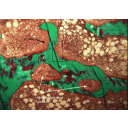

Osteitis_Fibrosis_Cystica.png